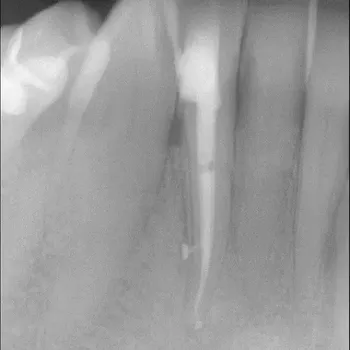

Fall 2: Entfernung eines Instrumentenfragmentes

Röntgenbild: Instrumentenfragment Ausgangssituation

Ausgangssituation